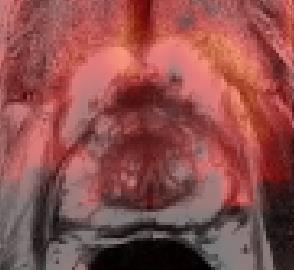

Prostate cancer biopsy benefits from accurate fusion of transrectal ultrasound (TRUS) and magnetic resonance (MR) images. In the past few years, convolutional neural networks (CNNs) have been proved powerful in extracting image features crucial for image registration. However, challenging applications and recent advances in computer vision suggest that CNNs are quite limited in its ability to understand spatial correspondence between features, a task in which the self-attention mechanism excels. This paper aims to develop a self-attention mechanism specifically for cross-modal image registration. Our proposed cross-modal attention block effectively maps each of the features in one volume to all features in the corresponding volume. Our experimental results demonstrate that a CNN network designed with the cross-modal attention block embedded outperforms an advanced CNN network 10 times of its size. We also incorporated visualization techniques to improve the interpretability of our network. The source code of our work is available at https://github.com/DIAL-RPI/Attention-Reg .